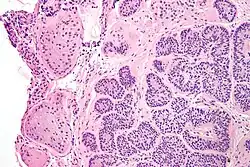

Micrograph of a Sertoli cell nodule. H&E stain.

Sertoli cell nodules are unencapsulated nodules that consist of:[2][3][4]

- cells arranged in well-formed tubules (that vaguely resemble immature Sertoli cells), with

- bland hyperchromatic oval/round nuclei that are stratified, and

- may contain eosinophilic (hyaline) blob in lumen (centre).